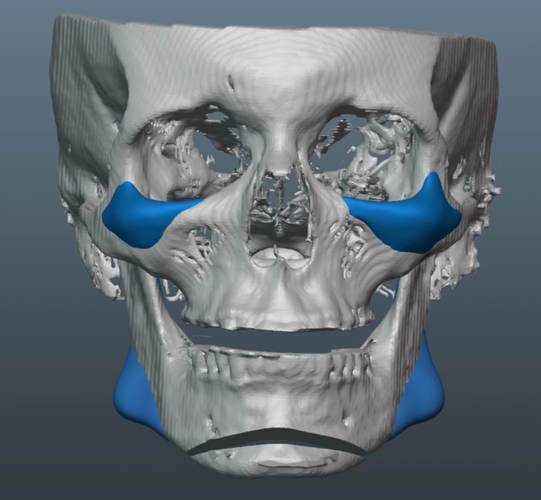

Just finished up this case and sent it to production.

-Patient also desired more volume around the infras and malars.

-Inframalars are 4.5mm and 5.5mm from 3/4 view.

-Infra rim shape has a slight, but improved, curve to keep a natural look.

Old silicone wraparound:

Old silicone wraparound: